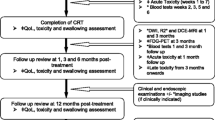

Patients in both studies underwent serial multiparametric MRI (DWI, T2) imaging before, during (weeks 2, 3, 5, 6), and following completion (1 month and 3 months) of radiotherapy. Patients also underwent 18F-FDG-PET/CT before and during (week 3) radiotherapy. The imaging timeline utilised in both studies is shown in Fig. 1. Treatment response was evaluated with post-treatment 18F-FDG-PET/CT and clinical examination including nasoendoscopy. Recurrences were confirmed histologically or via imaging following discussion at a multidisciplinary head and neck meeting.